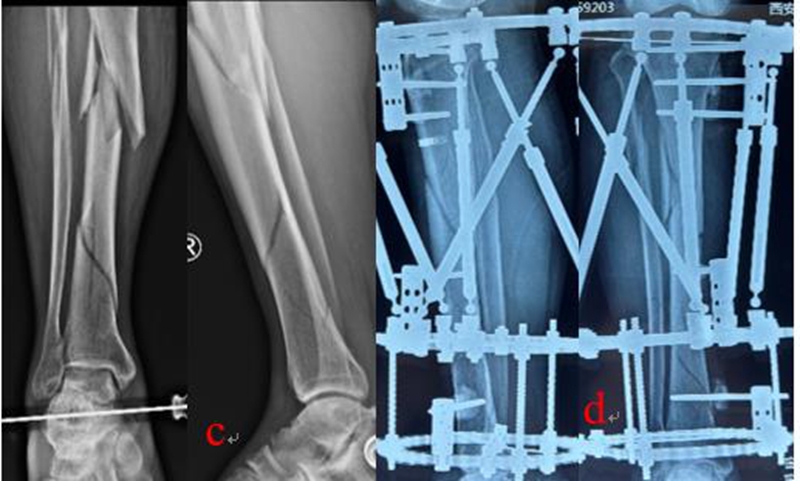

乔锋等[7-9]利用自主研发的3D打印骨科外固定架(QF)和数字六轴外架(QSF)治疗胫骨骨折,获得良好的临床疗效。3D打印骨科外固定架具有自动复位骨折功能,4根螺纹连接杆与骨的轴线平行,通过旋拧调节螺母,调节两个固定环之间的距离,实现对骨折断端轴向应力的调节和固定方式的转换,早期坚强固定,中期加压固定,后期弹性固定。复位过程无需透视,不依赖医生经验,手术时间短,可以不用麻醉,术后即可完全负重下地行走,复位精确,固定合理,操作简便。数字六轴外架QSF配套软件基于CT数据,与国际同类产品比较,复位精确,固定牢靠,操作简便,学习曲线短。

图1:QF治疗胫腓骨骨折

图2:QSF治疗胫腓骨骨折